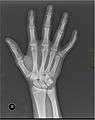

X-ray image of right hand with thumb on left.

Multiple fractures of the metacarpals (aka broken hand). (Right hand shown with thumb on left.)